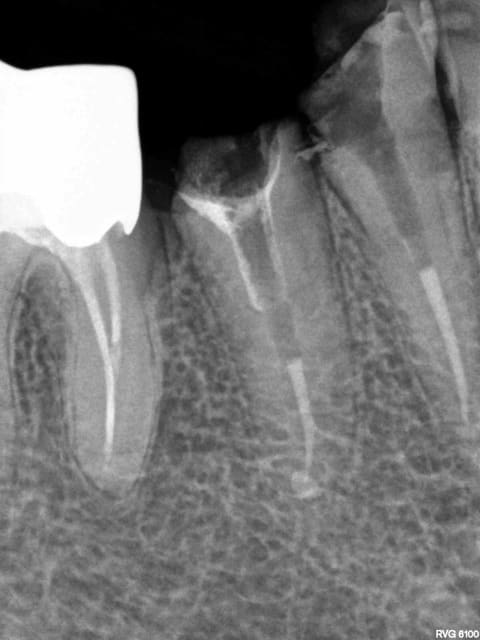

3 aujourd'hui avec celle là, petite journée -)))))

1 gyexyo - Eugenol

2 rmfjqv - Eugenol

3 yk9voc - Eugenol

5 s5asfw - Eugenol